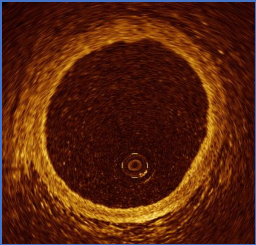

1. 血管三层结构

OCT可清晰显示血管内膜、中膜和外膜。内膜薄,明亮并且细密;中膜暗淡呈圆环状;外膜明亮略显疏松。三层结构OCT信号均匀,各向同向同性,衰减小,光可以完全透过。